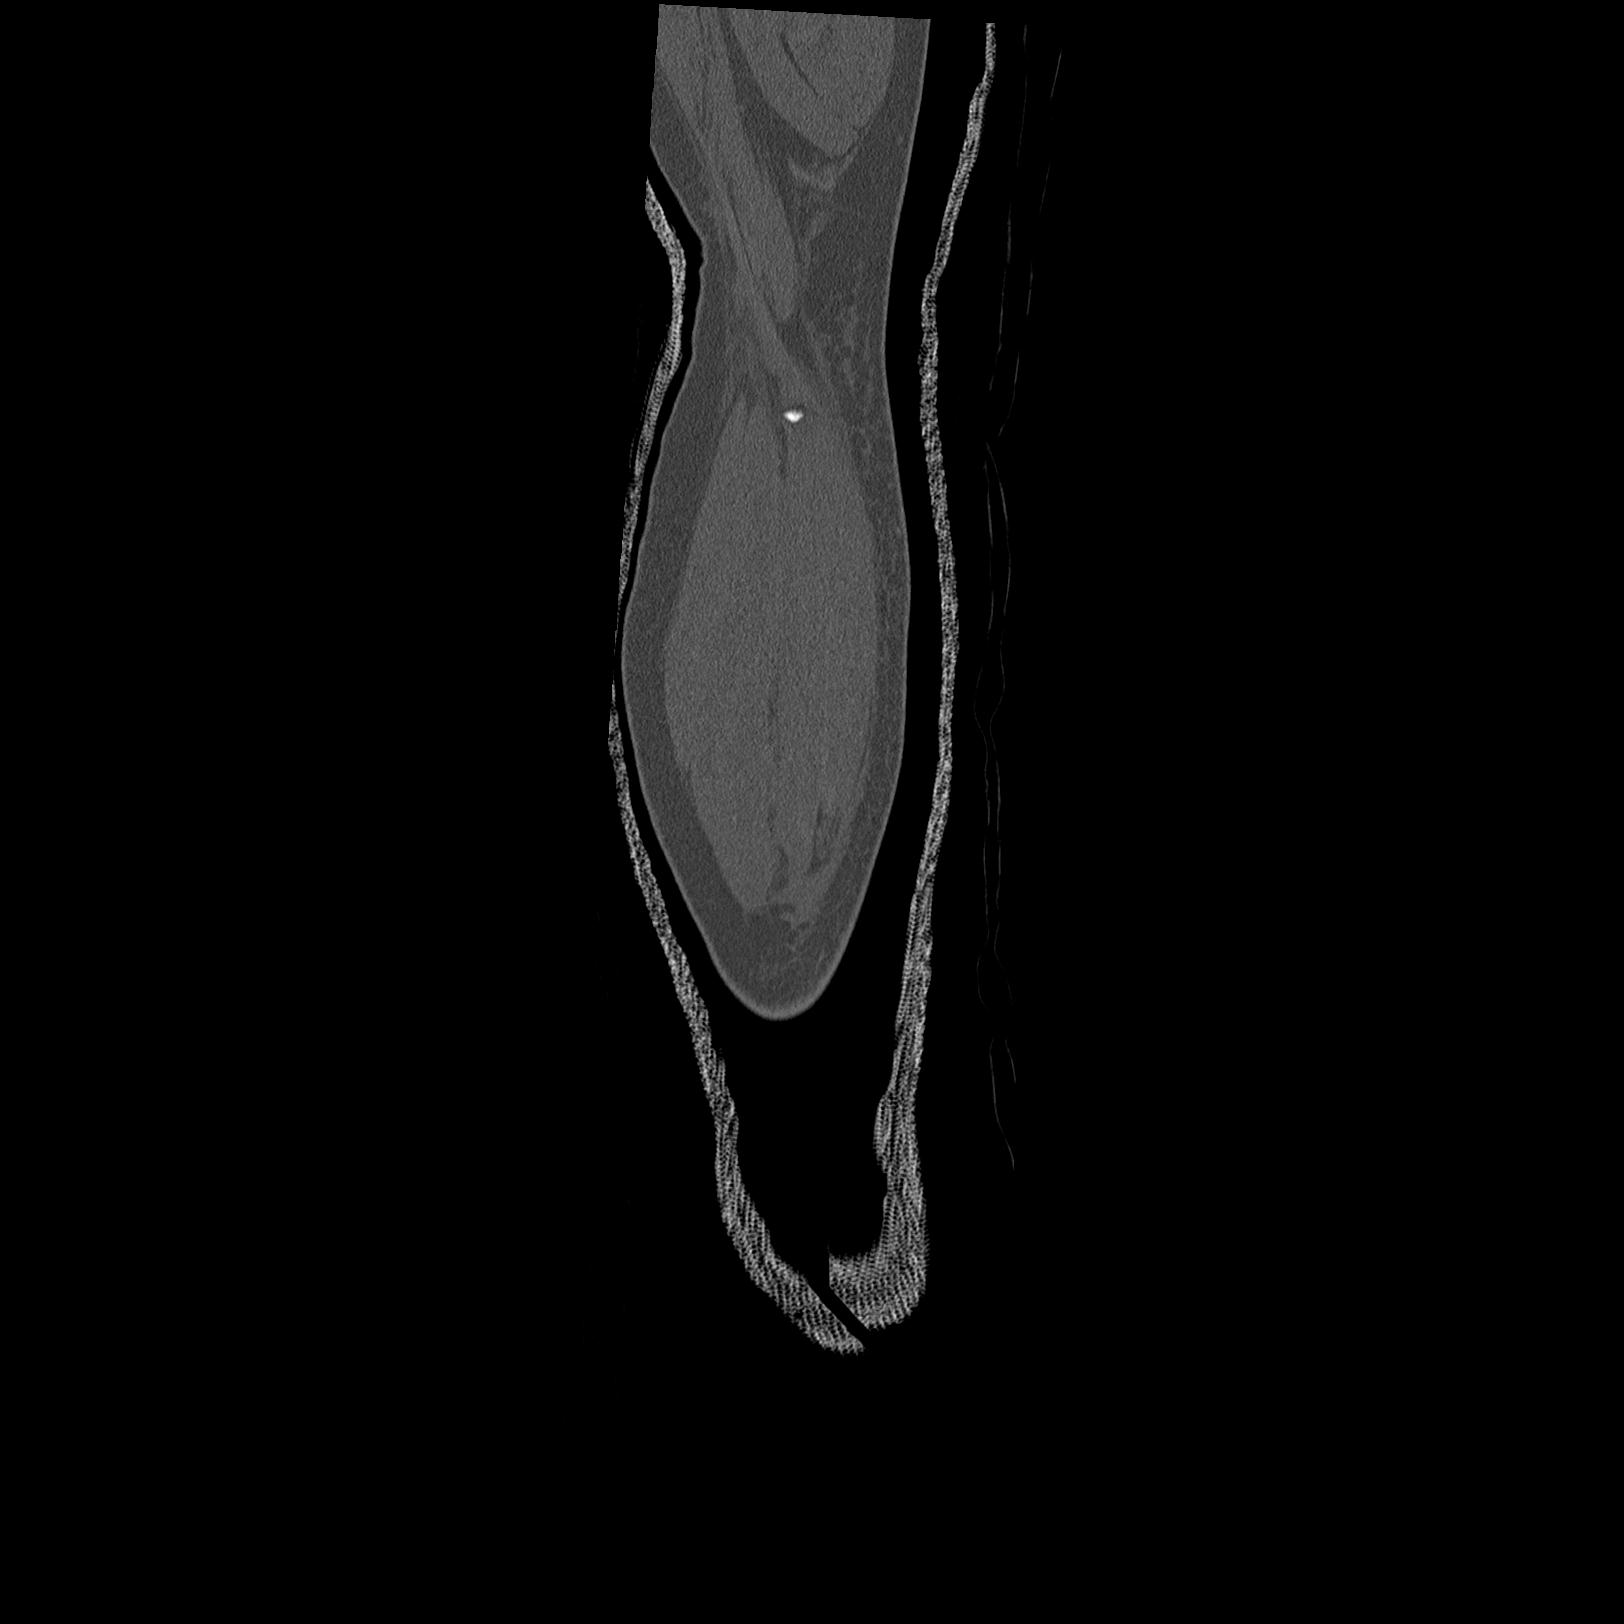

102803 1/12(キウスなし) 1/27 左下腿 4R 30歳女性 左脛骨軸内釘